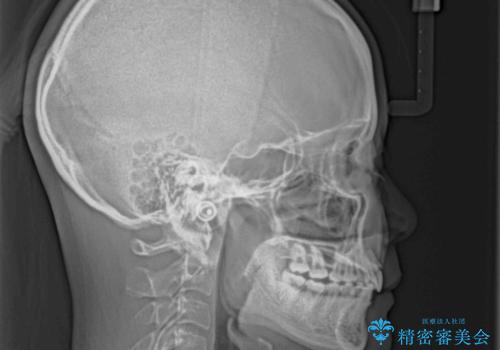

- 深い咬み合わせと上顎前歯の突出感を気にして来院された患者様です。

当院では通常、臼歯の咬合が理想的な位置に対して上顎が前方位にある場合。ワイヤー矯正または補助装置の併用したインビザライン矯正を選択しています。

正面や横からの写真ではきれいに治っており、患者様は大変満足のいく仕上がりとなりましたが、深い咬み合わせの改善は不十分で、奥歯の咬み合わせも改善させることができませんでした。

インビザラインは、咬合力の強い方ですと、奥歯が歯肉内にめり込んでしまうため、前歯が強く接触してしまうことがあります。

こちらの方は、奥歯はしっかりと噛んだのですが、歯肉にめり込んでしまったことで、歯肉が腫れやすくなってしまいました。